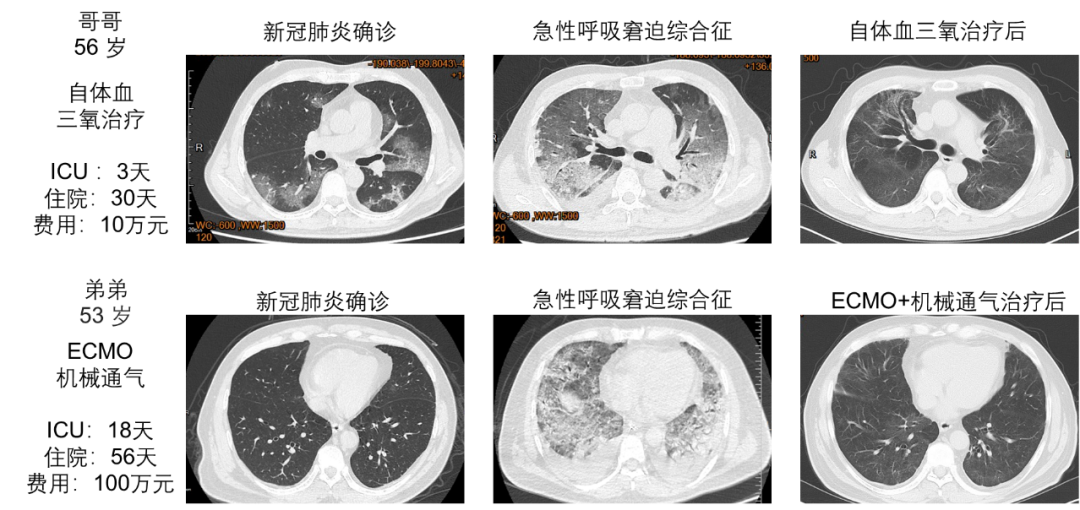

2月16日至17日,1 例重症和 2 例普通型患者(年龄为60-77岁)分别接受了自体血三氧治疗。治疗后,患者呼吸困难、剧烈咳嗽、胸闷乏力等症状均得到了明显改善,并逐渐康复,经专家组评估后均已顺利出院。特别值得一提的是,2月20日,1 例危重症患者(56岁)同意采用自体血三氧治疗,该患者的弟弟(几乎同时出现急性呼吸窘迫综合征)则实施机械通气(MV)、体外膜肺氧合(ECMO)等常规抢救措施。使用自体血三氧治疗患者(兄)第一次使用后氧合指数明显改善,连续使用9次后病情迅速缓解,影像学渗出影明显吸收,住院30天。与其相比,弟弟虽同样抢救成功,但住院天数长达56天,其治疗费用是其兄的10倍。

图2 自体血三氧治疗和ECMO常规抢救治疗患者医学影像对比